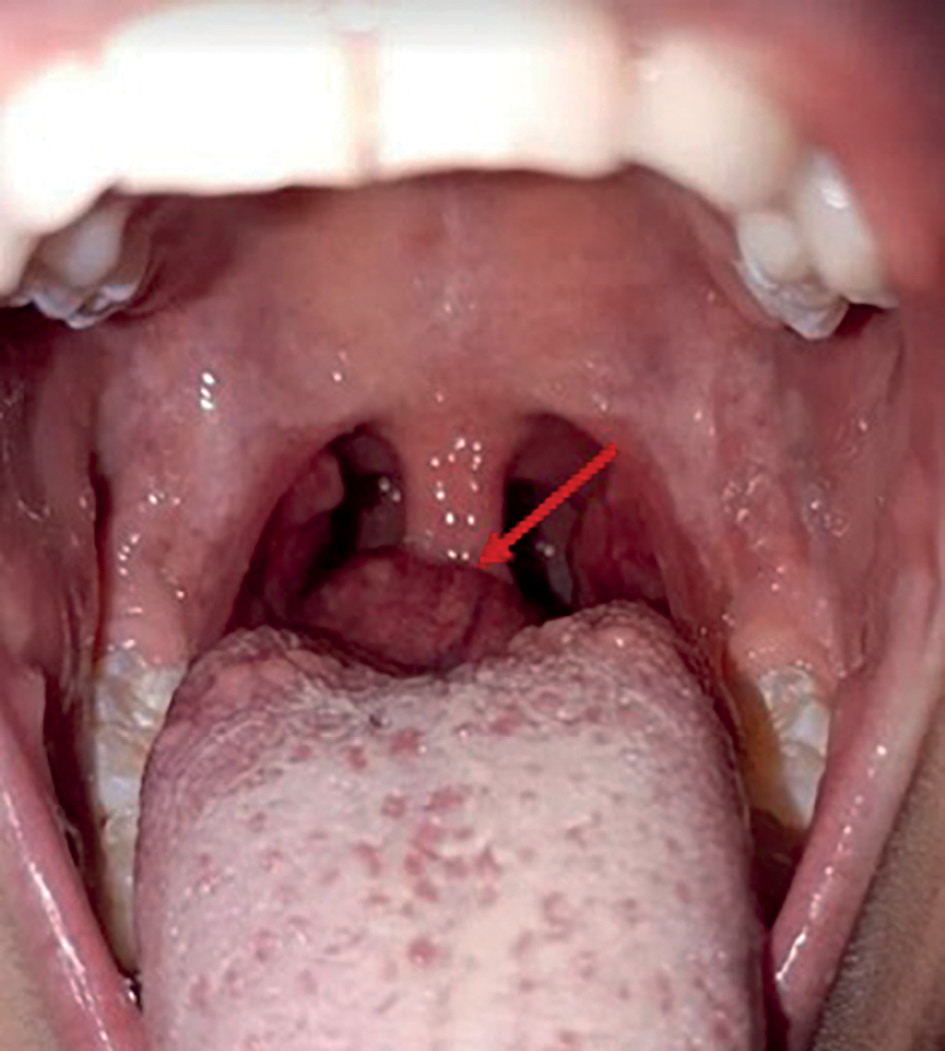

An 8-year-old female first was examined about neoplasm at the root of tongue at the age of 6.5. The patient was followed to ENT and diagnosed with lingual tonsil hypertrophy (Figure 2).

Figure 2. Ectopic thyroid tissue in the root of tongue observed during pharyngoscopy at the age of 6.5

At the age of 7.5, this patient the patient was admitted the National Endocrinology Research Centre for the first time. She complained of pain while swallowing and periodic cough. During pharyngoscopy a growth at the root of tongue was observed (Figure 5, a). Thepatient was seen by an otorhinolaryngologist; through a videofibrolaryngoscopy, a nodular growth was clearly identified (Figure 5, b).

Figure 5. Ectopic thyroid tissue in the root of tongue as observed through pharyngoscopy (a) and videofibrolaryngoscopy (b) in a 7.5-year-old patient